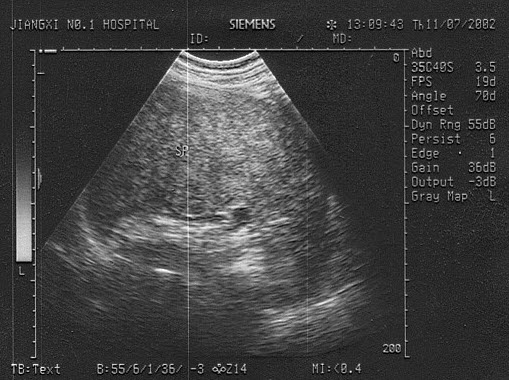

某患者脾脏声像图表现如图,诊断为()

A.正常脾脏

B.脾大

C.脾破裂

D.脾梗死

E.以上都不是